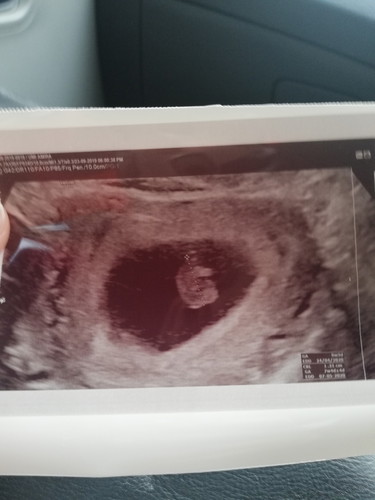

Hai mommies... this is my second pregnancy.. the first one miscarriage.. second pregnancy plk scan.. nmpak kantung je dua minggu lpas.. doct soh dtg balik dua minggu kmudian.. so hari nie scan balik kat klinik.. Alhamdulillah... nmpak baby nye.. all my worries goneee..! but.. the doct said no heart beat.. so she referred me to hospital.. doct cek.. he said.. with heavy heart.. ur baby da xde... lagi dua minggu kite cek skali lagi.. mane tahu miracle happens.. I cried heavily.. two times pantang tanpa baby..